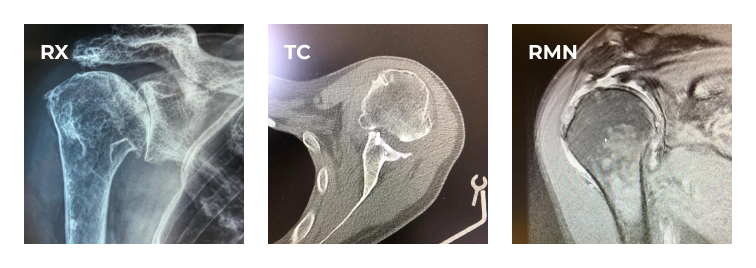

L’artrosi di spalla

L’usura della cartilagine tipica dell’artrosi di spalla provoca un’alterata distribuzione delle forze nell’articolazione gleno-omerale con successivi cambiamenti anche dal punto di vista anatomico. L’artrosi di spalla è quindi una patologia disabilitante, che causa dolore, limitazione funzionale e instabilità.